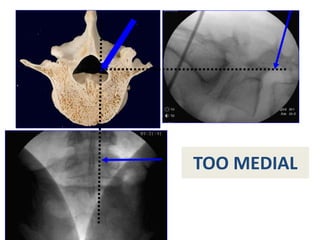

Pictorial of trajectory ‘‘stopping points’’

to ensure safe placement of the Jamshidi needle

ENTRY POINT

MID-PEDICLE

NC JUNCTION

TOO MEDIAL

TOO LATERAL

Technique

The needle is then advanced through the pedicle

to the dorsal aspect of the vertebral body

The intersection of the

pedicle and vertebral

body is the critical

junction. If the needle is

not medial to the medial

wall when the needle is

at this depth, then a safe

trajectory has been

found.

Key point

Medial pedicle wall at

posterior vertebral body or deeper

Safety for injection